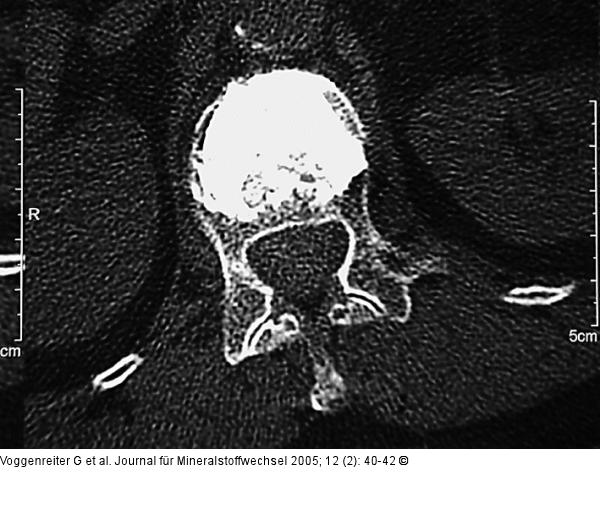

Abbildung 4a-d: Wirbelkörperaufrichtung - postoperative Darstellung Postoperative Darstellung der Zementverteilung und der Wirbelkörperaufrichtung im CT. Trotz Beteiligung der Wirbelkörperhinterkante kam es zu keiner weiteren Einengung des Spinalkanals, sondern durch Ligamentotaxis eher zu einer Erweiterung. Das postoperative Kontroll-CT zeigt eine Reduktion der Kyphose bei klinischer Beschwerdefreiheit der Patientin. |

Postoperative Darstellung der Zementverteilung und der Wirbelkörperaufrichtung im CT. Trotz Beteiligung der Wirbelkörperhinterkante kam es zu keiner weiteren Einengung des Spinalkanals, sondern durch Ligamentotaxis eher zu einer Erweiterung. Das postoperative Kontroll-CT zeigt eine Reduktion der Kyphose bei klinischer Beschwerdefreiheit der Patientin. |